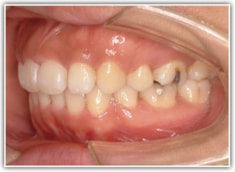

上顎前突ケース

治療法:表の矯正(T21ブラケット)

治療前